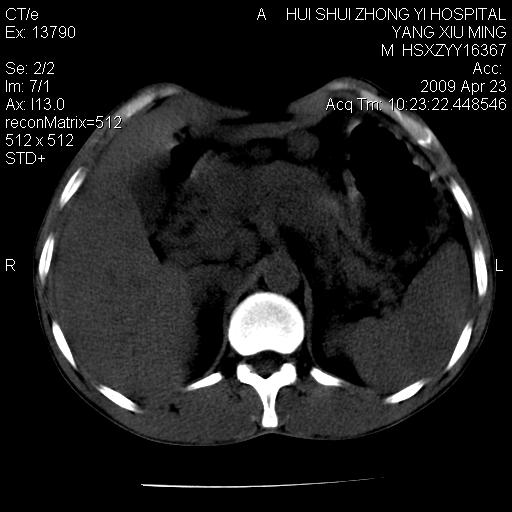

上腹部疼痛一月,呕吐10天,发现左侧颈部包快10天 胸部cr片未见明显异常。

腹膜后淋巴结增大,转移、淋巴瘤?胰腺增大,胰腺炎?占位?颈部考虑增大淋巴结。建议腹部增强扫描。

黑!广泛淋巴结肿大不符合胰腺癌转移。胰腺周围淋巴结肿大致使胰腺看起来大。考虑淋巴瘤可能大。

缺少强化资料,暂考虑胰腺癌广泛转移.